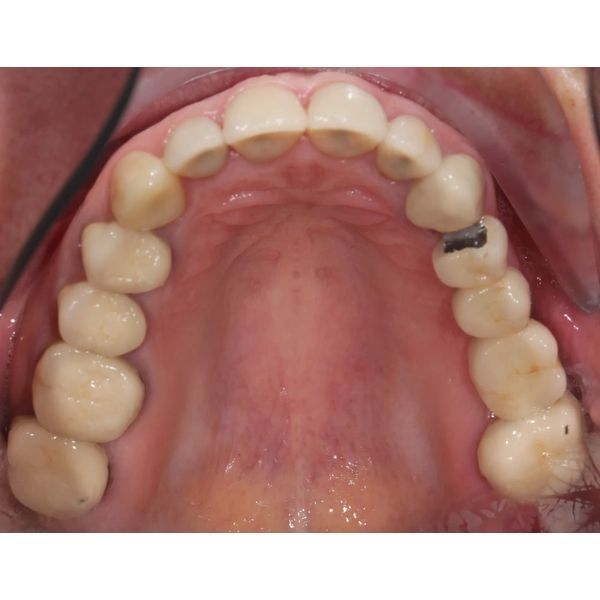

При осмотре выяснилось, что конструкции на центральных зубах хоть и выглядели эстетично, на них появились трещины и сколы, было нарушено краевое прилегание. Кроме того, у женщины наблюдалась стираемость зубов, особенно заметно стёрся нижний клык (зуб 3.3). На других зубах также присутствовали сколы.

Десневой контур был неровным, а сама десна в ряде участков выглядела нездоровой, что могло быть вызвано краевым прилеганием конструкций и неидеальной гигиеной.

Жевательные поверхности боковых зубов оставались гладкими. Это говорило о том, что у пациентки не было окклюзионных помех, которые могли бы спровоцировать проблемы с височно-нижнечелюстным суставом (ВНЧС), однако из-за отсутствия рельефа контакт между зубами-антагонистами плоскостной, а не точечный, поэтому мышцам приходилось прилагать больше усилий, чтобы пережевать пищу.